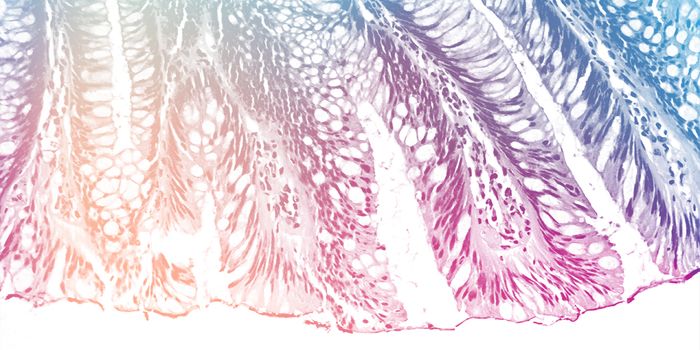

SEP 28, 2016ImmunologyA diet high in fat from specific sources is uniquely responsible for contributing to intestinal cancer through promoting ...

NOV 05, 2016Cell & Molecular BiologyNew research published in the Journal of Biological Chemistry outlines how certain cells in the intestine, enterocytes, ...

SEP 26, 2023MicrobiologyInflammatory bowel diseases (IBDs) include Crohn's disease and ulcerative colitis, in which the gastrointestinal tra ...

NOV 01, 2021Cell & Molecular BiologyInflammatory bowel disease (IBD) is a term that describes chronic gut inflammation and includes ulcerative colitis and C ...